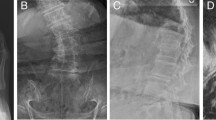

Summary: Thirty-three families of indivduals with a history of spina bifida, with myelomeningocele were studied. Each member was HLA typed and had a spinal X-ray. The incidence of spina bifida occulta, and laminal asymmetry of the lumbo-sacral spine in sibs and parents is high. No association between these abnormalities the HLA system was found.